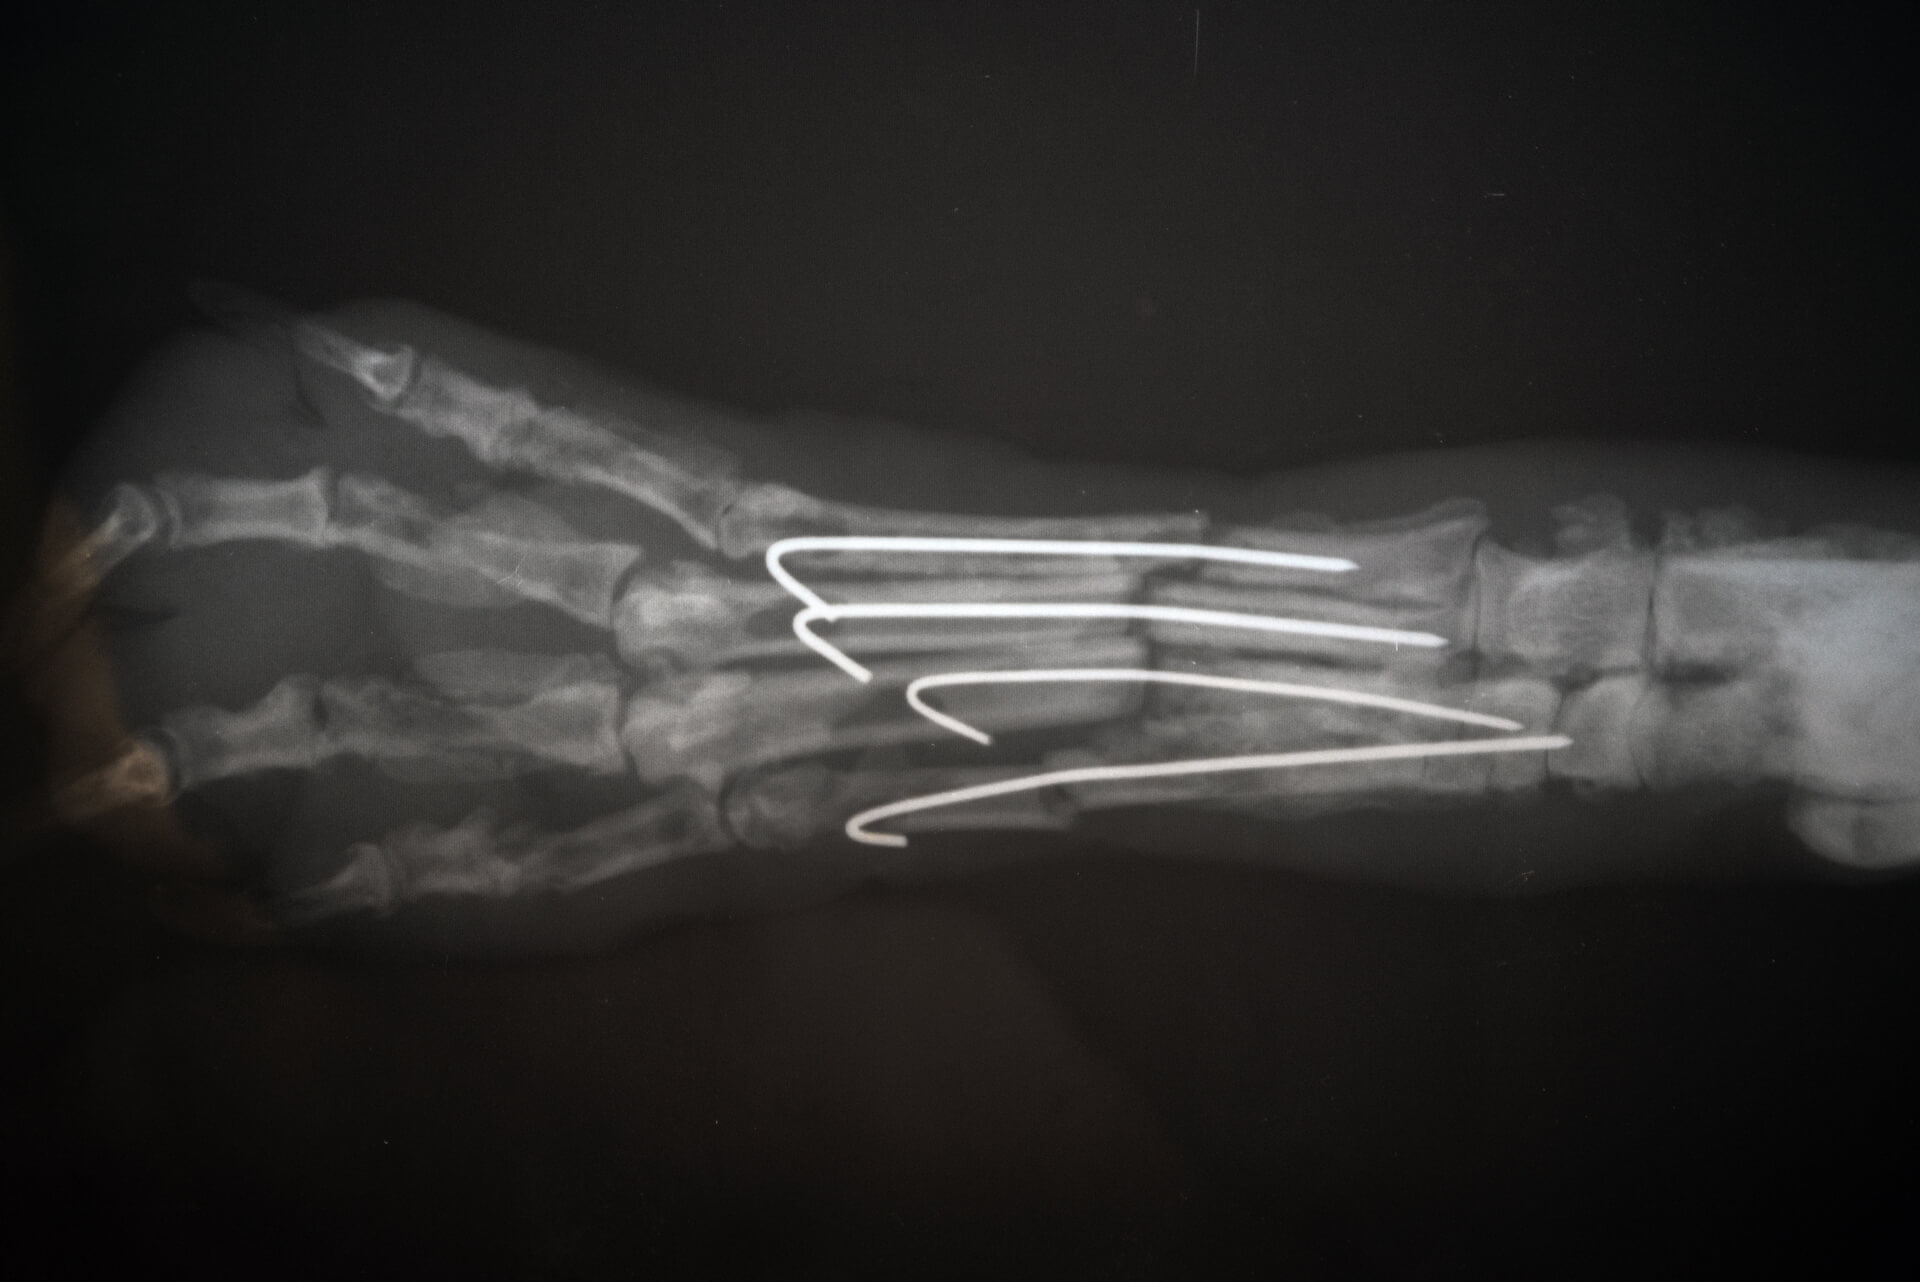

Durante essa avaliação, são observados sinais de claudicação e possíveis atrofias musculares. É fundamental examinar o desenvolvimento muscular e determinar qual membro foi afetado. Após essa análise preliminar, o veterinário realiza a palpação do membro e conduz exames complementares, como radiografias, para confirmar o diagnóstico e o grau da lesão.

• Cirurgias ortopédicas: Procedimentos cirúrgicos para corrigir lesões mais graves, como fraturas complexas e deslocamentos articulares.